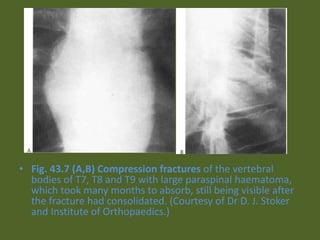

• Fig. 43.7 (A,B) Compression fractures of the vertebral

bodies of T7, T8 and T9 with large paraspinal haematoma,

which took many months to absorb, still being visible after

the fracture had consolidated. (Courtesy of Dr D. J. Stoker

and Institute of Orthopaedics.)

• Fig. 43.7(A,B) Compression fractures of the vertebral bodies of T7, T8 and T9 with large paraspinal haematoma, which took many months to absorb, still being visible after the fracture had consolidated. (Courtesy of Dr D. J. Stoker and Institute of Orthopaedics.)